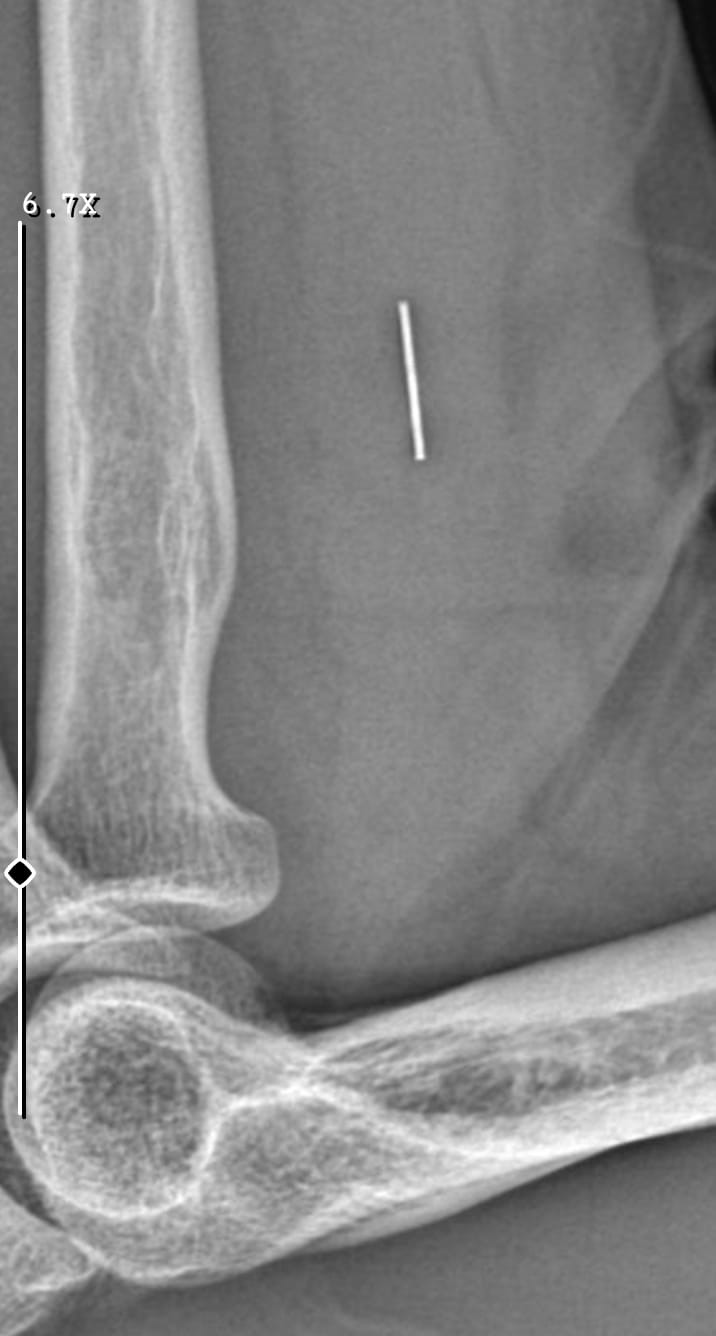

Öte yandan, ameliyatların ardından ağrıları devam eden Güleryüz’ün kolunda metal parça bulunduğu ve bu parçanın parmak bölgesinden dirseğe doğru ilerlediği öne sürüldü. Ayrıca, fabrikada temizlik personeli olarak çalışan Nurettin Güleryüz’ün hastane sürecinde işten çıkarıldığı da öğrenildi.

“Doktorlara bileğime doğru ağrılarım olduğunu sürekli ifade etmeme rağmen beni dinlemediler. Sonradan kolumda metal kaldığını öğrendik. Bunun ihmal olduğunu düşünüyoruz. Çünkü kola metal nasıl girebilir? Ben 9 aydır çalışamıyorum. Kalp rahatsızlığım sebebiyle yüzde 46 engelliyken şu anda yüzde 75 engelli durumuna düştüm. Erken emeklilik dilekçesi verdim ancak henüz sonuç gelmedi. Bu konuda çok mağdurum. Yetkililerin bunu duymasını istiyorum. Savcılığa suç duyurusunda bulunduk. Yaklaşık 9 aydır henüz soruşturma izni gelmedi. Süreci bekliyoruz, henüz dava açılmış değil. Kolumda bırakılan metal ilerliyor. Pazartesi günü bunun için de operasyon geçireceğim. Çıkarılıp çıkarılamayacağı net değil. Elimde titremelerim var, çalışamıyorum ve işveren tarafından işten çıkarıldım. Yetkililerden destek ve konunun incelenmesini talep ediyorum. ”